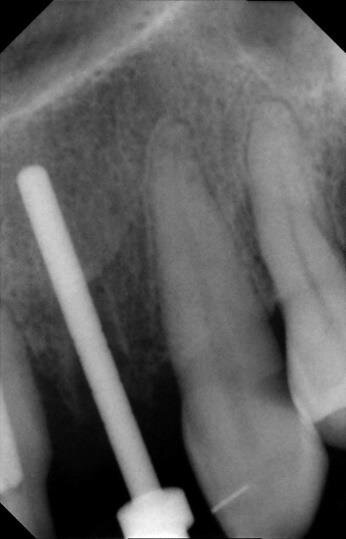

Tutto ciò viene dettagliatamente spiegato sia verbalmente, sia descritto nel “Consenso informato” che la paziente sottoscrive dopo aver richiesto un secondo consulto presso un altro studio. Il trattamento estrusivo dei due incisivi laterali inizia nel gennaio 2011 (Figg. 7, 8). Al raggiungimento del risultato desiderato (Figg. 9, 10), si attendono 60 giorni di “stabilizzazione” dell’osso alveolare18 (Figg. 11, 12).

La fase chirurgica viene pianificata con la preparazione iniziale (igiene orale, controllo emato-chimico delle condizioni della paziente, prescrizione della profilassi/terapia antibiotica19-20 e della sospensione del fumo). Il 23 giugno 2011, vengono estratti i due incisivi laterali (Figg. 13, 14) e inseriti contestualmente due impianti Xive (Dentsply) di diametro 3,8 mm e lunghezza 15 mm (Figg. 15, 16), dimensioni ottimali per la successiva protesi (ponte di 4 elementi da 1.2 a 2.2 con 1.1 e 2.1, elementi “intermedi”).